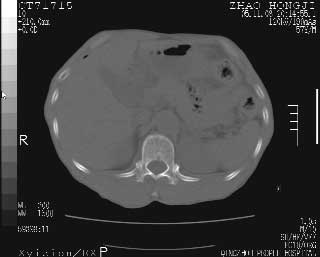

临床资料:男性,57岁,上腹部疼痛并5天,突然加重并延及全腹伴恶心5小时入院。胰淀粉酶化验在正常范围。检查:腹肌紧张,全腹压痛、反跳痛,尤以右上腹部为著。肠鸣音减低。血常规:wbc14.6x10/9, n:11.3x10/9 ,血压:135/90mmhg. 胸部透视:腹部肠腔轻度张气,未见其它异常改变。

肝右前缘少量积气,其他未见明显异常.考虑上消化道穿孔.

小网膜囊积气液,胃壁僵硬。考虑胃穿孔。

小膜网膜积液,肝缘气腹征,上消化道穿孔。

肝缘见少许气体,胰尾部见少许气体包饶(蓝色圈),12指肠上部或球部邻近胆囊周边也可见少许气体影(黄色圈),并忖托出胆囊壁,12指肠远段肠道内未见明显气体(白色箭)。

肝脏前缘见少量积气、胰尾部见少许气体包饶,肾前筋膜未见增厚,临床淀粉酶不高,意见:上消化道穿孔。

消化道穿孔。12指肠球部周和胰周积气考虑12指肠穿孔可能性大。

入院3小时后行剖腹探查术,见腹腔内大量脓性混浊液约1000ml,十二指肠球部溃疡穿孔,溃疡面约2.5x2cm,穿孔直径约0.6cm。胃内容物外益,周围组织炎性水肿明显。行十二指肠穿孔修补术。术后诊断:

1、十二指肠溃疡穿孔

2、弥漫性腹膜炎

对于少量的腹腔游离气体,ct检查较普通透视有绝对的优势,它不仅可以看到肝脏前上缘的气体,而且还能够看到小网膜区的游离气体。从而可以肯定诊断。各位分析战友的很好,感谢大家的参入!